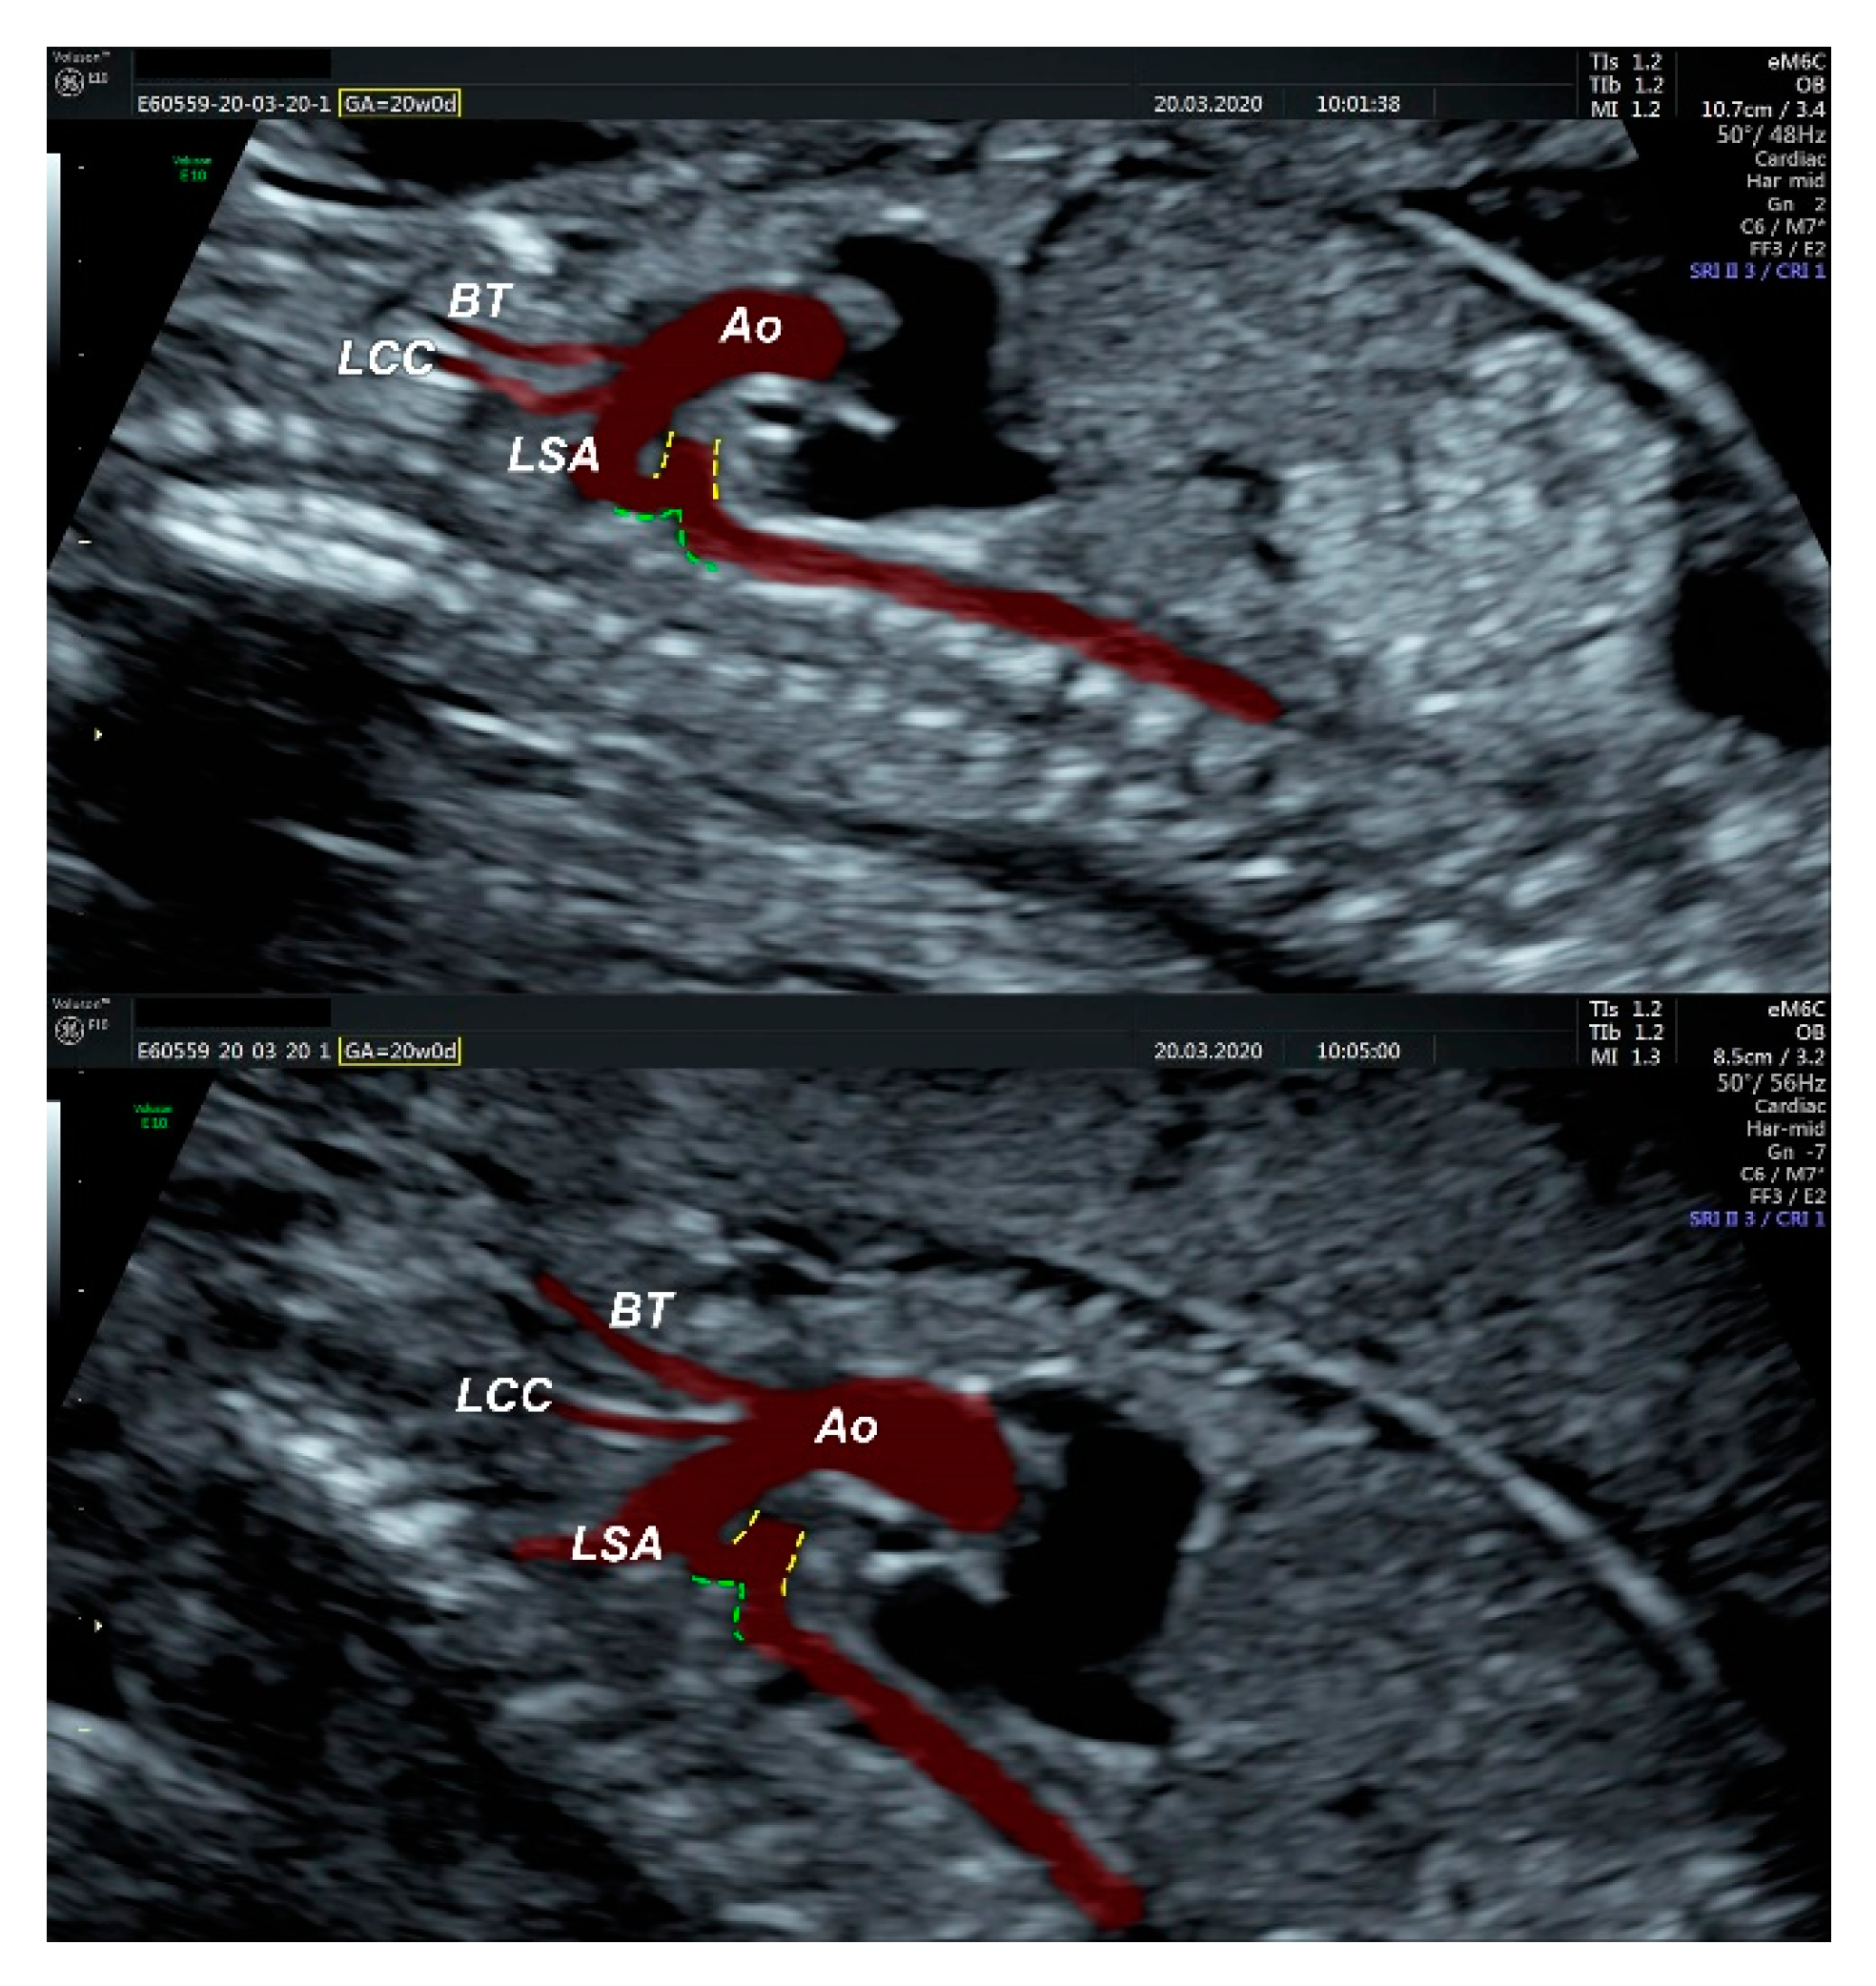

2.1. Ultrasound Findings

- an isolated aortic arch anomaly (supposedly aneurysmal dilation from which the left common carotid artery emerges) and coarctation of the aorta with the anterograde flow;

- ventricular septal defect, coarctation of the aorta, and a vascular formation located superior from the aortic arch with the appearance of an arteriovenous fistula;

- aneurysmal dilation located above the pulmonary trunk bifurcation and a dilated left common carotid artery with a retrograde flow;

2.2. Dissection